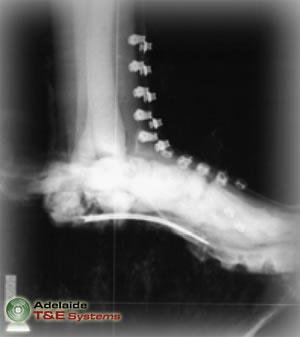

The principal method of injury assessment is standard medical examination, both physically and radiographically, to diagnose outcomes that often include dislocations, fractures and traumatic amputations.

The flash x-ray images above show the FSLLM’s response in millisecond intervals to 50g of plastic explosive buried 20mm below sand with 50mm of standoff. Note: images sourced from DSTO-TR-1829.